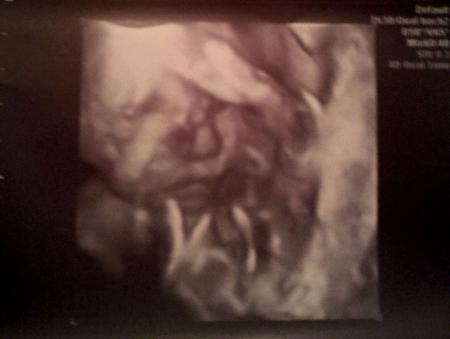

Und das war sooo toll. Unser kleine Mann und das ist mehr als 100% eindeutig ein Junge, ist sooo gelenkig. Er hat nach ein paar Bildern ständig den Fuß im Gesicht gehabt. Außerdem fand unsere FA, dass er eine sehr starke Mimik hat. Er hat ne Schnute geschnitte, dann gelacht, dann gegähnt, dann sozusagen geredet und dann wieder so getan als wenn er singen würde ^^ war voll lustig. und er ist sooo süß Wir haben auf jeden fall gesheen, dass er total glücklich und freudig ist. er grinst ganz oft :-D Übrigens wurde nochmal vermessen. Größe haben wir jetzt nicht erfahren..ist irgendwie unter gegangen, aber er wiegt etwa 700g und laut dem berechnen stand da ET 12.05. und mein eigentlicher ET ist 22.05. Na mal sehen. also ändern tun wir das nun erstmal nicht mit dem 22.05. hab aber eh schon im gefühl, dass er früher kommen wird. Jetzt spann ich euch nicht mehr so auf die Folter. Ich hab ganz viele Bilder und hab euch mal die 4 schönsten raus gesucht. Und die kommen jetzt :-)

Bild zu Zurück vom 3D US :-D - Forum für Mai - Mamis